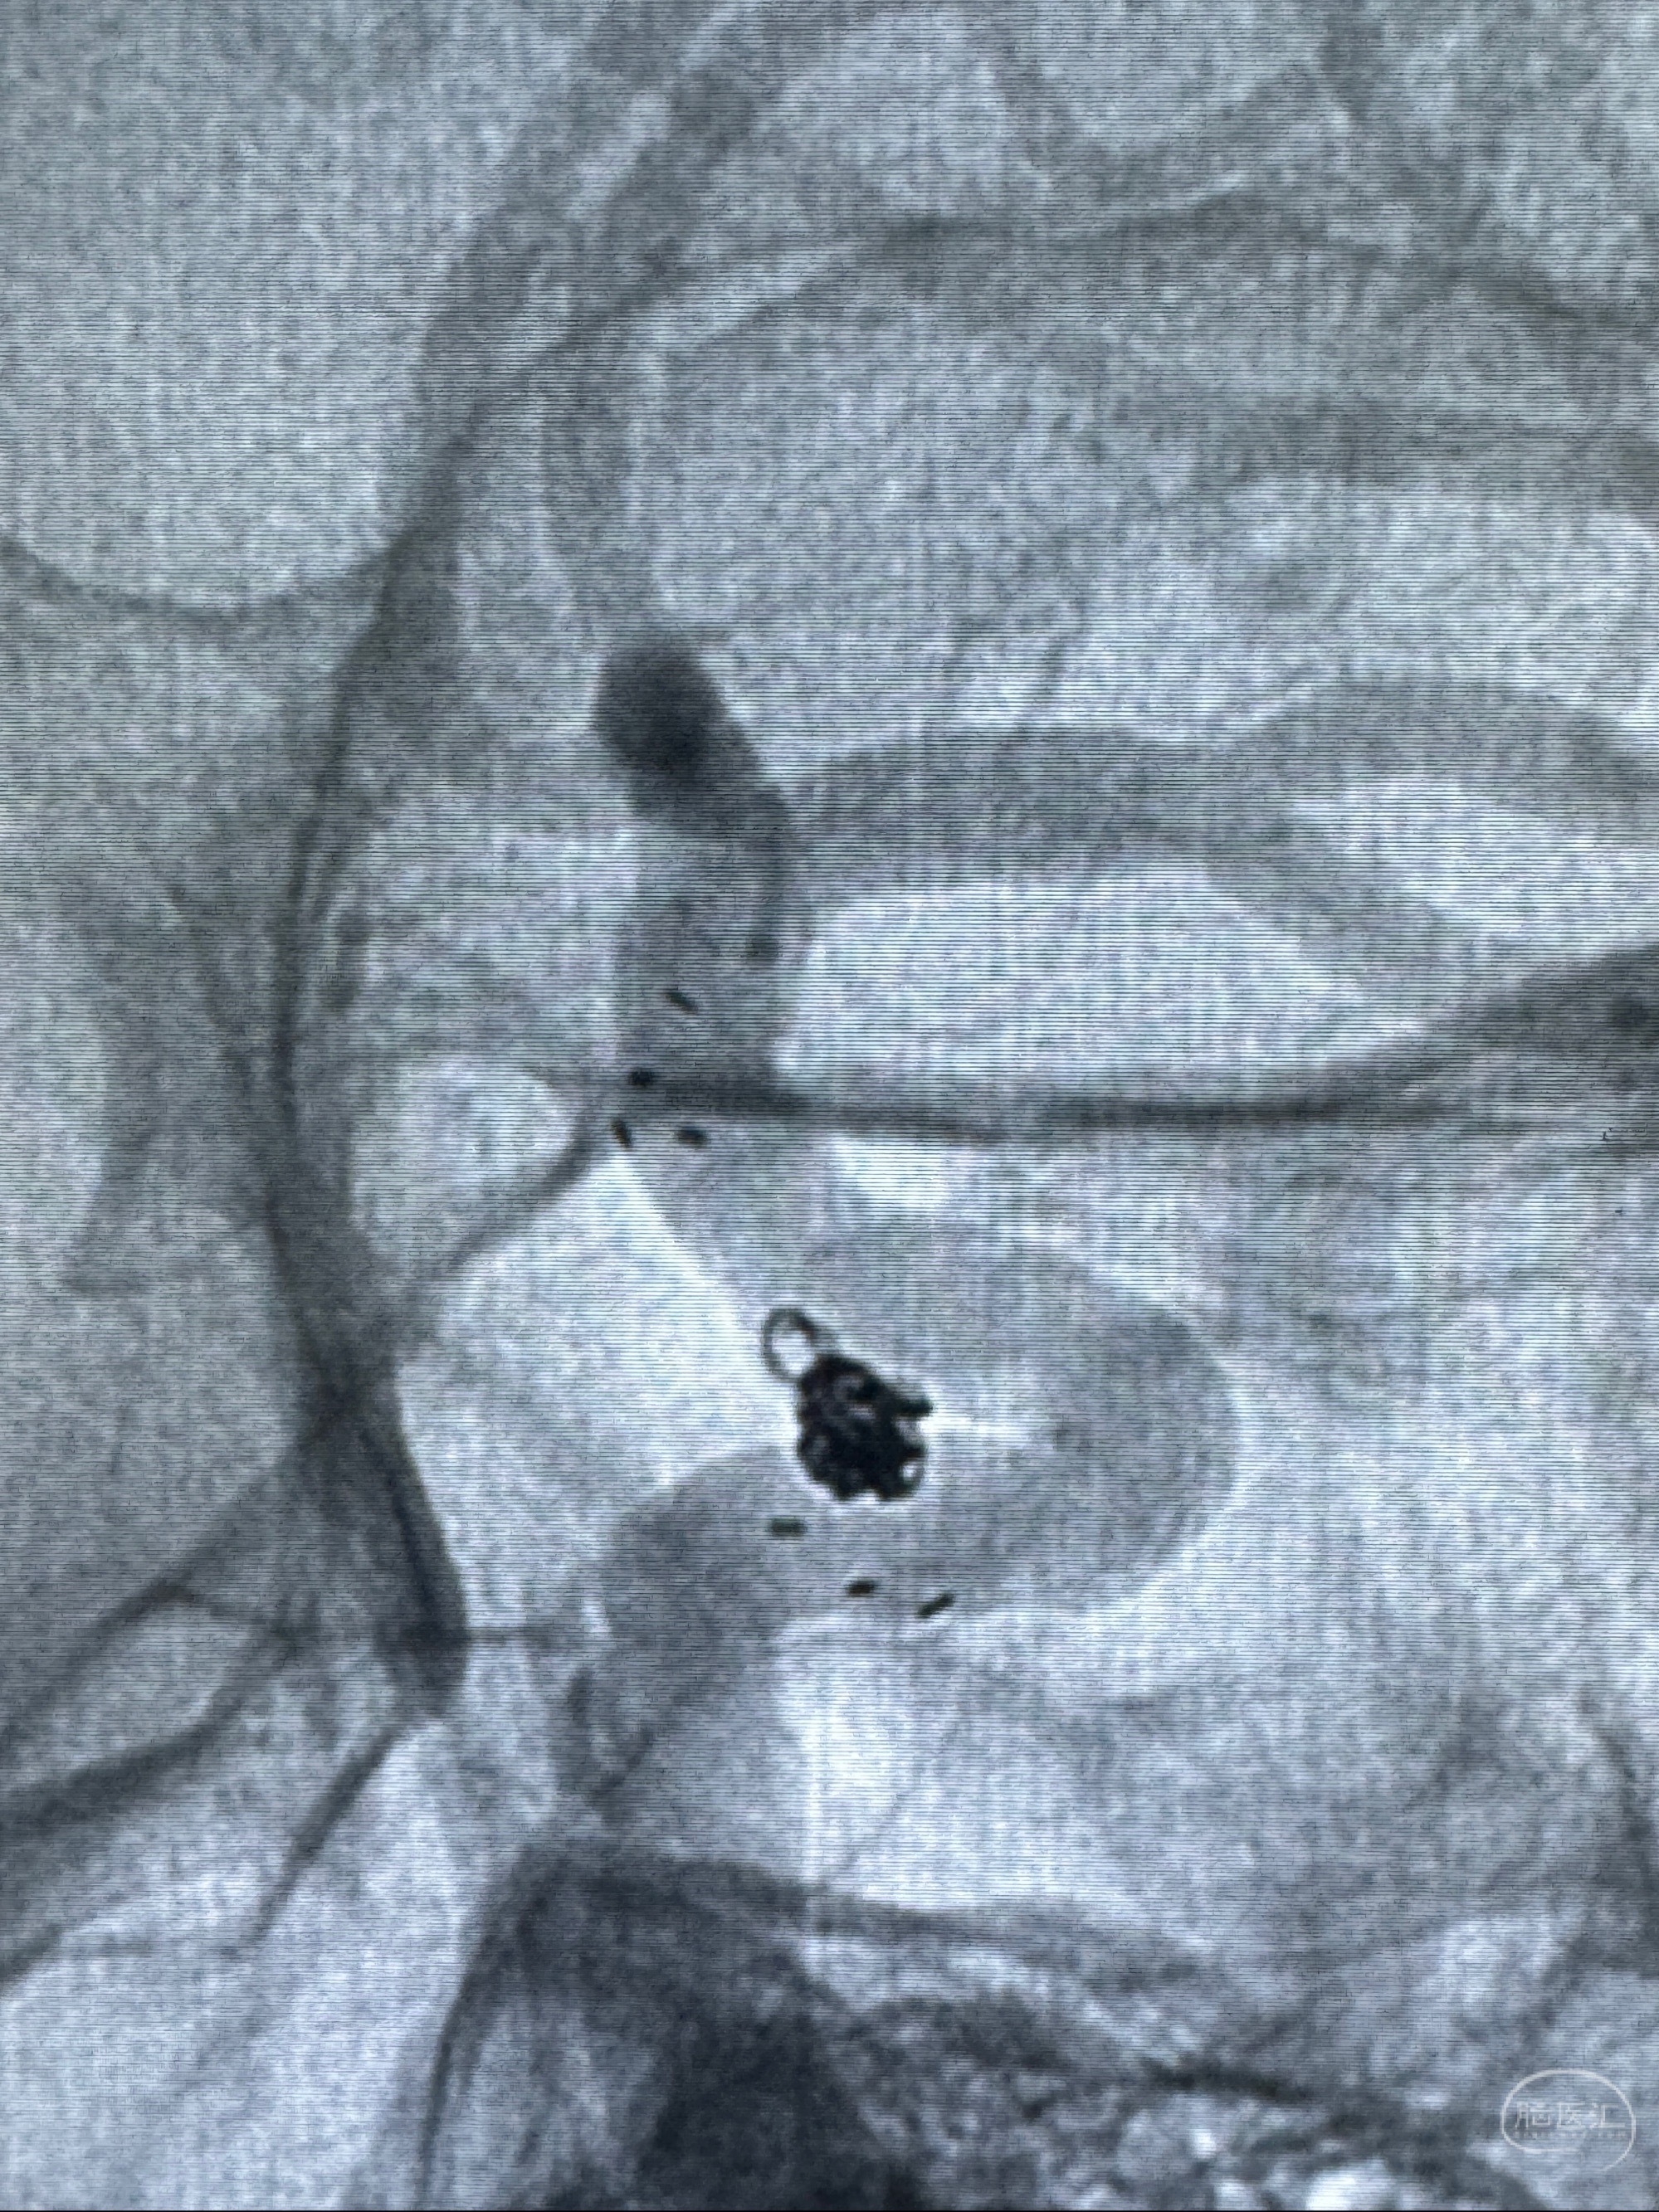

2023-11-29全麻下行NeuroformEZ4.5-20mm支架辅助栓塞

麻醉苏醒佳,遵嘱动作

术后即刻CT